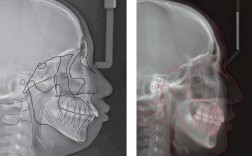

| 头颅侧位片 | 分析颅面骨骼的形态、位置关系(如SNA角、SNB角、ANB角),评估面部软组织轮廓,判断骨性畸形类型 | 骨性错颌畸形诊断,制定拔牙方案,预测矫正后面型变化 |